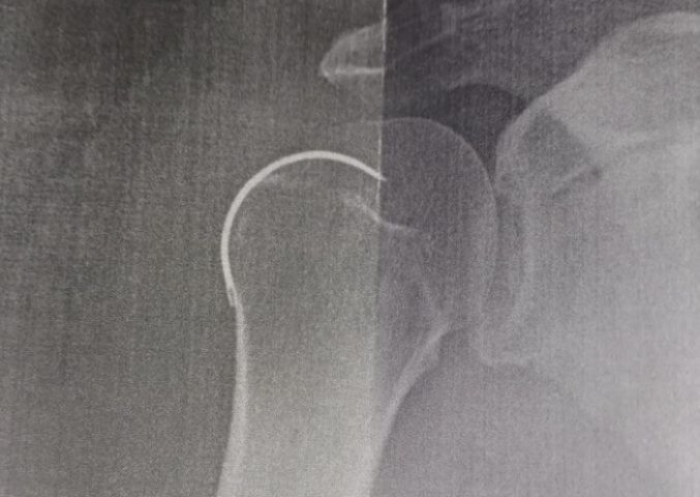

Uma agulha foi esquecida dentro de um paciente durante uma cirurgia no ombro direito, realizada no Hospital Santo Antônio, em Armazém.

O morador de Capivari de Baixo, de 62 anos, foi submetido ao procedimento em 6 de outubro do ano passado e somente na última semana o objeto foi retirado. Segundo ele, o médico teria esquecido a agulha de sutura dentro do ombro.

Contudo, ao realizar um novo raio-X, os médicos descobriram a presença da agulha. A retirada do objeto cirúrgico aconteceu na última semana, também no Hospital Santo Antônio.